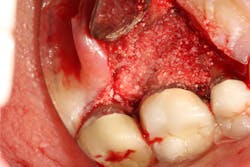

Bone defects that have three to four walls missing are the hardest to repair and may be slated for extraction (figure 6). By adding growth-stimulating factors to your regular bone grafts (figure 7), an increase in osteopromotive potential occurs that can have the ability to overcome a deficiency of bone walls.15 Simply stated, your bone graft can become alive, and teeth that were once unable to be repaired now have a chance.

Figure 6: Molar tooth with three walls missing around the palatal root. This tooth would normally be extracted.

Figure 7: Same tooth undergoing periodontal regeneration surgery with anorganic bovine bone (Bio-Oss Collagen, Geistlich Biomaterials) and platelet-derived growth factor (PDGF)